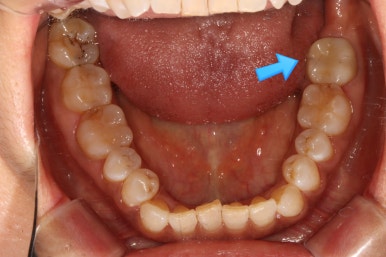

화살표로 가리치고 있는 치아의 불편감을 호소하고 계셨습니다.

보시다시피, 아래턱 큰어금니의 씹는면에 약간의 충치가 있는바.. 일단 레진으로 떼우기로 치료계획을 세웠었죠.

레진으로 떼워도 아프다고 하셨습니다.